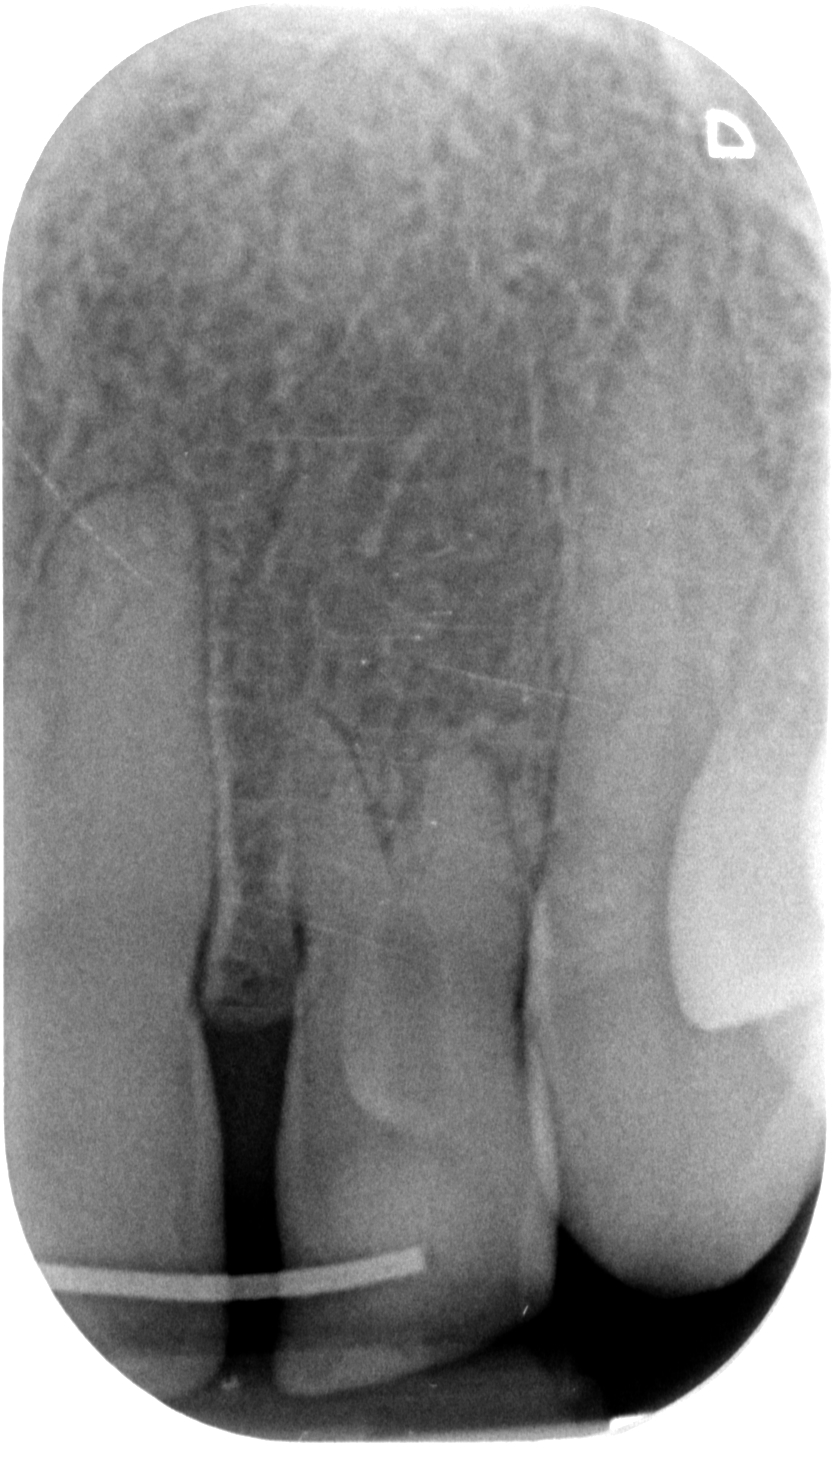

L’anomalia del dentone nella radiografia qui sopra forse è un po’ più facile da riconoscere, ma non sono comunque sicuro che tutti i dentisti sappiano di cosa si tratti e, soprattutto, abbiano idea di che trattamento eseguire.

Il fenomeno rappresentato è chiaramente un Dens Invaginatus, meglio conosciuto come Dens in Dente. In realtà esiste una terza definizione, che è quella della mia assistente Roberta che è portatrice sana di un Dancing Dente ???, che è quello che ha capito lei quando ho emesso la diagnosi guardando la rx del suo incisivo laterale di sinistra! Diagnosi che il suo vecchio dentista non aveva saputo fare…

Con tutta probabilità l’affondamento del dente da latte sulla gemma in formazione del 2.2 ha generato una deformazione dell’organo dello smalto che si è appunto invaginato all’interno della papilla dentale, formando un dens in dente, come dimostra la linea radiopaca che si intravede all’interno del dente, che non è nient’altro che smalto. Uno smalto un po’ meno mineralizzato di quello esterno, se guardiamo alla letteratura, ma pur sempre smalto.

Ora Maddalena, così si chiama la ragazzina di questo dens in dente, con un piccolo allungamento di corona clinica seguito da limatura del margine incisale e una semplice otturazione di 12 e una corona in disilicato preparata su questo dens in dente, può tornare a sorridere. Ecco la foto e la rx a sei mesi dal caso finito. Tutto perfetto! Il 22 sta guarendo e le gengive e i denti stanno alla grande! Il brillantino invece ha perso il diamantino! ?